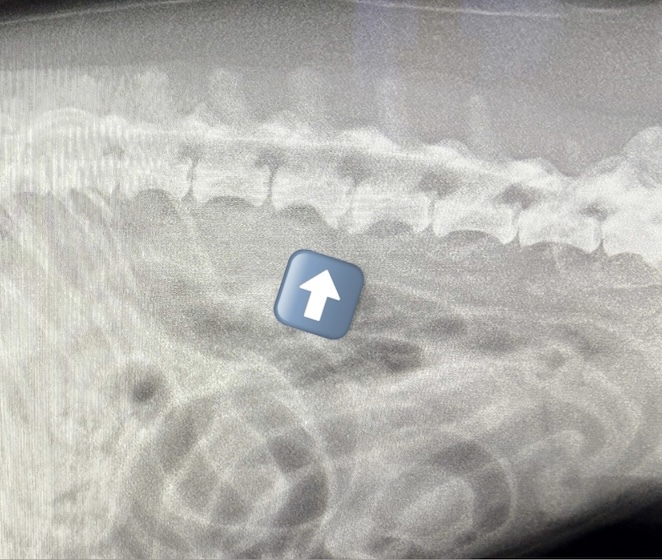

変形性脊椎症(2025/12/08)

変形性脊椎症は、身体を支えている背骨(脊椎)が年齢とともに少しずつ変形してしまう病気です。多くは無症状なためレントゲン検査で偶然見つかることも珍しくありません。しかし、変形した脊椎が神経を圧迫することで痛みや歩行異常が現れることがあります。椎間板の変性や加齢による椎体間の不安定性が原因と考えられています。症状が見られる場合は、鎮痛剤で痛みを和らげたり、温熱療法などの理学療法で筋肉の緊張をほぐしながら経過を見ていきます。最近活動量が減ってきた、歩きにくそうにしている、などの変化は病気のサインかもしれません。なにか気になる症状があればお気軽にご相談下さい。

犬の変形性脊椎症(2024/12/07)

変形性脊椎症とは身体の構造を支えている脊椎に変形が起こってしまう病気です。多くは無症状で健康診断などで偶発的に発見される事があります。しかし変形した脊椎が神経を圧迫する事でまれに痛みや運動障害を引き起こす事があります。治療は症状がある場合は鎮痛剤の投与や、温熱治療などの理学療法を行って痛みを緩和していきます。また肥満の場合には脊椎に過度な負荷をかけてしまうため、適切な体重管理が重要となります。お家のわんちゃんが高齢になって活動性が落ちてきた、歩きにくそうにしているなど気になる症状がありましたら、お気軽にご相談ください。